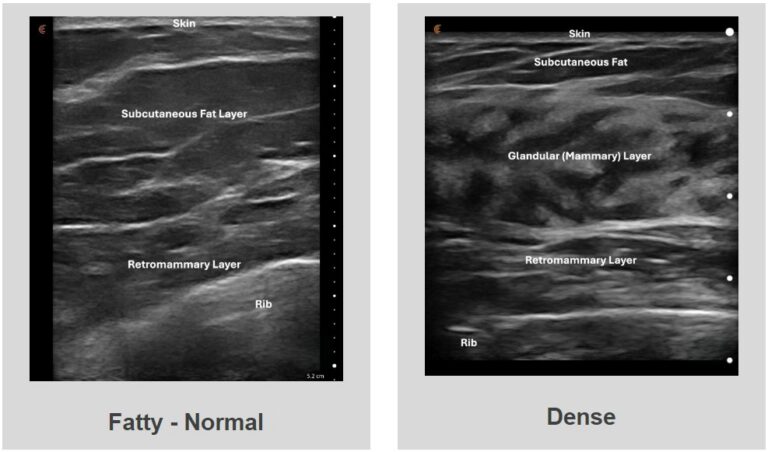

Understanding the Difference Between a Regular and Dense Breast Tissue

Fatty – Normal Dense Understanding the Difference Between a Regular and Dense Breast Tissue Women are diagnosed with dense fibrous breast